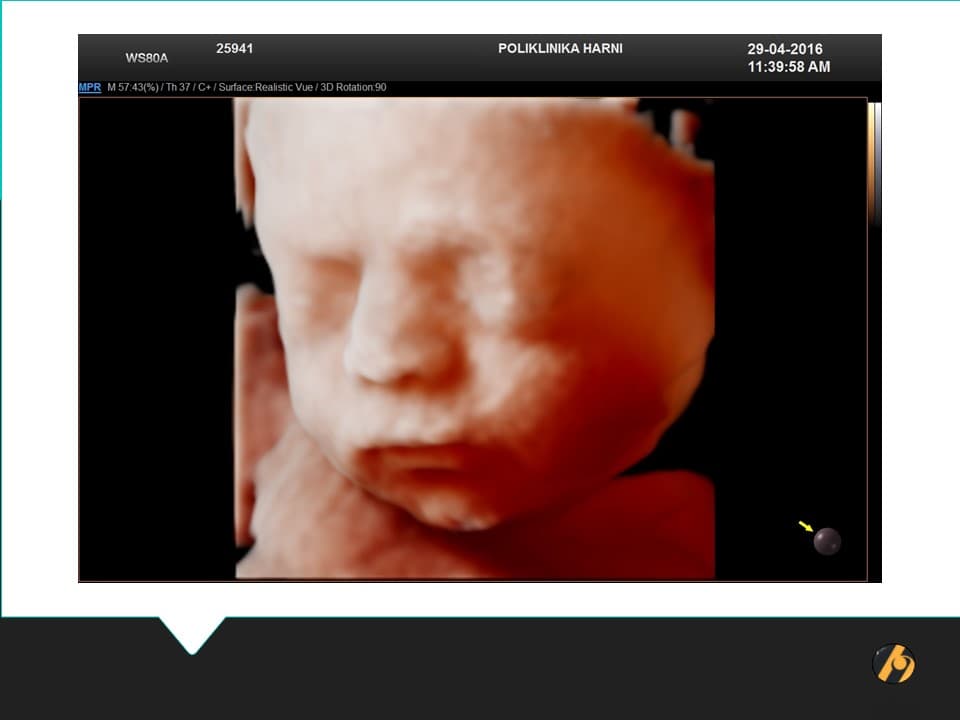

Bez obzira kakva će boja očiju vaše bebe biti kasnije, za vrijeme intrauterinog života, oči vaše bebe su plave boje. U ovome tjednu beba otvara oči, koje su sada u potpunosti razvijene i imaju sve slojeve: bjeloočnicu, rožnicu, šarenicu i mrežnicu. Mrežnica ima sve slojeve kao i nakon porođaja. Sada su formirane i minijaturne trepavice i obrve, koje će dalje rasti sve do porođaja. Pored toga, ovaj tjedan se počinju otvarati i nosnice bebe, što joj omogućuje vježbanje disanja uz pomoć mišića prsnog koša i pluća.

Vaša beba dugačka je oko 35 cm, teška 700 - 850 g i veličinom odgovara glavici salate.